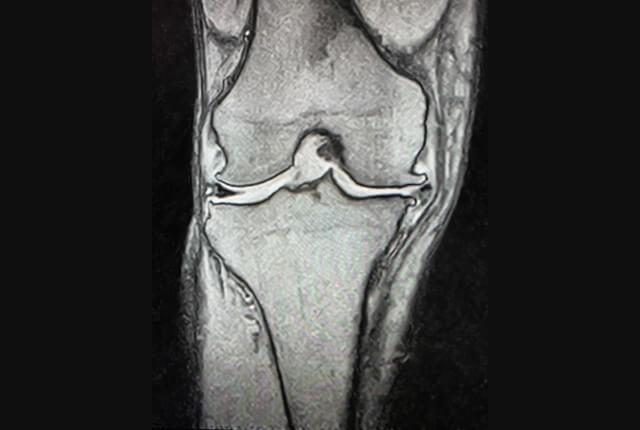

前十字靱帯損傷、半月板損傷

前十字靭帯(ACL)は大腿骨と脛骨をつなぐ靱帯で、後十字靭帯と交差する様に前方に存在します。

半月板は大腿骨と脛骨の間にある線維軟骨です。内側半月板と外側半月板があり、C型の形状をしています。

診断

• MRIでACL損傷や半月板損傷を確定診断